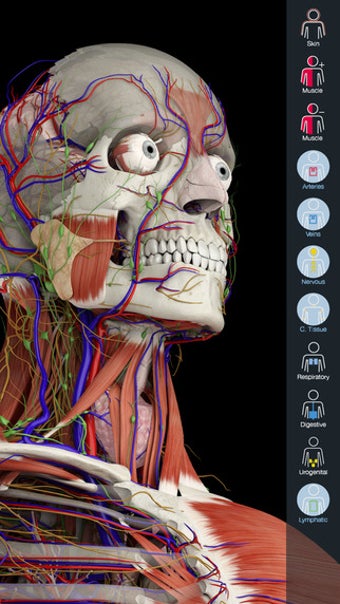

Essential Anatomy 3 ไม่ใช่การปฏิวัติในซีรีส์แอป Essential Anatomy แต่เพิ่มรายละเอียดและใช้งานง่ายขึ้น ไปที่แอป สิ่งที่น่าประทับใจที่สุดเกี่ยวกับ Essential Anatomy 3 คือ ระดับของรายละเอียดและโมเดล 3 มิติ ที่คุณสามารถจัดการและสำรวจได้ Essential Anatomy 3 ทำให้ไม่เปิดเผยอวัยวะหรือเอ็น - ระดับของรายละเอียดดีพอๆ กับสิ่งที่คุณพบในสารานุกรมทางการแพทย์

สำหรับนักศึกษาแพทย์โดยเฉพาะ Essential Anatomy เป็นเครื่องมืออ้างอิงที่ยอดเยี่ยม โมเดล 3 มิติช่วยให้คุณดูและตรวจสอบส่วนต่างๆ ของร่างกายมนุษย์ได้จากทุกมุม โดยให้รายละเอียดที่น่าทึ่งซึ่งปกติแล้วคุณจะสัมผัสได้ผ่านการผ่าเท่านั้น

Essential Anatomy ใช้งานง่ายมาก ฟังก์ชันการค้นหาคือสิ่งที่คุณต้องการมากที่สุดหากคุณกำลังเรียนอยู่ แม้ว่าคุณจะสนุกสนานไปกับการสำรวจและหมุนร่างกายก็ตาม คุณสามารถแยกชั้นของกล้ามเนื้อและเนื้อเยื่อออกเพื่อเผยให้เห็นสิ่งที่อยู่ภายใต้ ซึ่งจะช่วยให้คุณมีความคิดที่ดีขึ้นมากเกี่ยวกับการทำงานของร่างกาย มากกว่าที่จะอ่านมันในหนังสือ

นอกจากนั้น ยังมี เครื่องมือบุ๊กมาร์ก หากคุณต้องการบันทึกเฉพาะส่วนที่ต้องการย้อนกลับไปดูในภายหลัง และคุณสามารถแยกมุมมองร่างกายตามประเภทของชิ้นส่วน (เช่น กล้ามเนื้อ หลอดเลือดแดง เส้นเลือด ฯลฯ)